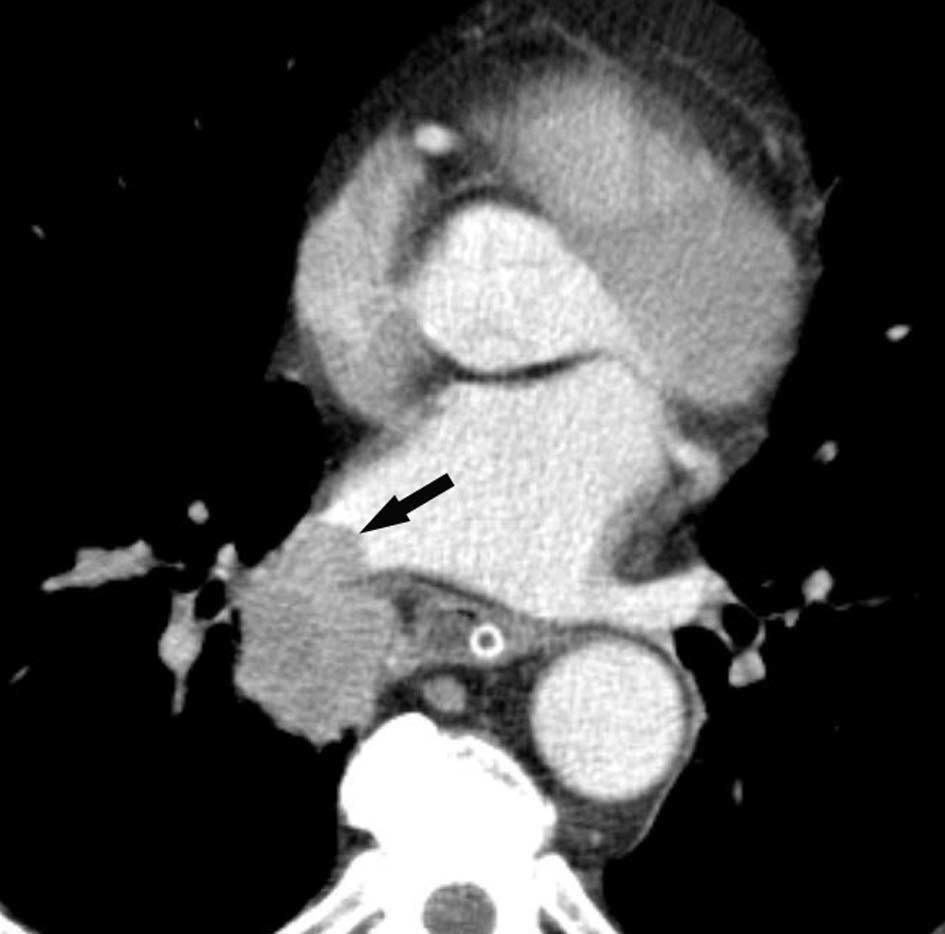

Fig. 4.--Invasión vascular. Tomografía computarizada (TC) torácica con contraste. Corte axial (A) y reconstrucción coronal oblicua (B). Invasión tumoral por continuidad de la vena pulmonar inferior (flecha).

Pese a las conocidas limitaciones de la TC, ésta continúa siendo la técnica de elección en la estadificación del tumor en los pacientes con CPNM; su sensibilidad y especificidad en la determinación de la infiltración de pared oscilan entre el 38 y el 87% y del 40 al 90%, respectivamente, según las series. El desarrollo de nuevos equipos de TC helicoidal y principalmente las TC multidetectoras (TCMD) proporcionan unas imágenes 2D de mayor resolución con la posibilidad de hacer reconstrucciones multiplanares (MPR) en distintos planos del espacio e incluso 3D con la consiguiente mejora de la valoración del tumor, su extensión e infiltración de estructuras vecinas5 (fig. 4). Así, con la TCMD se puede poner de manifiesto con mayor fiabilidad la invasión de la cisura, la pared torácica o el mediastino, y además es capaz de determinar, gracias a las reconstrucciones de volumen, la relación exacta del tumor con la vía aérea (fig. 5). El progreso en la capacidad diagnóstica deriva del incremento en la resolución de las imágenes obtenidas y de la posibilidad de emplear nuevas aplicaciones como la broncoscopia virtual y la visualización en tiempo real. La broncoscopia virtual es útil para valorar la invasión del árbol traqueobronquial con la finalidad de planificar la cirugía, también como guía para el fibrobroncoscopista y, por último, porque permite ver el árbol bronquial distal a la estenosis (fig. 6)6. La capacidad de ver la imagen en tiempo real es especialmente útil cuando se emplea como guía en maniobras intervencionistas como biopsias percutáneas, ya sea con finalidad diagnóstica o como parte de la estadificación (fig. 7). Esta técnica de guía de biopsia denominada TC fluoroscopia reduce el número de pases y el tiempo global de la exploración, implica un menor riesgo de lesión de estructuras y permite la visualización inmediata de las posibles complicaciones7.